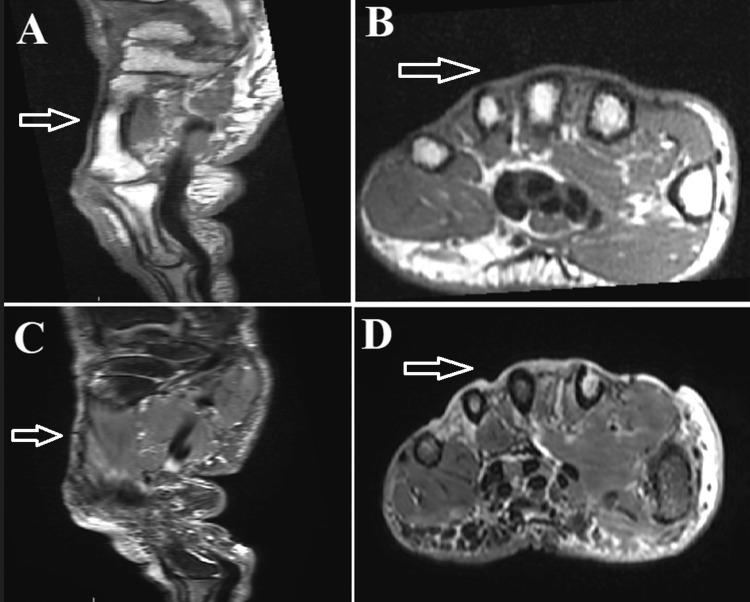

This case report describes the successful use of Integra® (Integra LifeSciences Corporation, Plainsboro, New Jersey, United States), an artificial skin substitute, for the reconstruction of soft tissue defects following soft tissue sarcoma resection. We present a case of a 75-year-old female presented with a progressively enlarging lesion on her right hand. Imaging revealed tumor involvement in the extensor tendons and adjacent to the index finger tendon. A percutaneous biopsy confirmed an undifferentiated pleomorphic sarcoma. The patient underwent neoadjuvant radiotherapy followed by wide excision of the tumor. Integra® dermal regeneration matrix was utilized to cover the exposed bone during the surgical procedure. This allowed for wound closure and provided a favorable environment for tissue regeneration and subsequent split-thickness skin graft. Complete wound healing was obtained. Regular follow-up examinations showed no evidence of local recurrence or secondary lesions after one year. The successful use of Integra®, in this case, demonstrates its efficacy as a reconstructive option for complex hand sarcomas. It offers immediate wound coverage and promotes tissue regeneration, thereby avoiding the need for more extensive treatment modalities with associated donor-site morbidity. The utilization of Integra® resulted in high patient satisfaction and excellent recovery. This case highlights the importance of utilizing innovative techniques and materials in achieving optimal outcomes in challenging hand sarcoma reconstructions.

本病例报告描述了使用人工皮肤替代品Integra®(美国新泽西州普林斯顿平原boro的Integra生命科学公司)成功重建软组织肉瘤切除术后软组织缺损的情况。我们报告一例75岁女性,右手出现逐渐增大的病变。影像学检查显示肿瘤累及伸肌腱并靠近示指肌腱。经皮活检证实为未分化多形性肉瘤。患者接受了新辅助放疗,随后进行了肿瘤广泛切除。手术过程中使用Integra®真皮再生基质覆盖暴露的骨骼。这实现了伤口闭合,并为组织再生和随后的中厚皮片移植提供了有利环境。伤口完全愈合。定期随访检查显示,一年后无局部复发或继发病变的迹象。在本病例中,Integra®的成功使用证明了其作为复杂手部肉瘤重建选择的有效性。它能立即覆盖伤口并促进组织再生,从而避免了需要更广泛的治疗方式及其相关的供区并发症。Integra®的使用使患者满意度高且恢复良好。本病例突出了在具有挑战性的手部肉瘤重建中利用创新技术和材料以实现最佳结果的重要性。